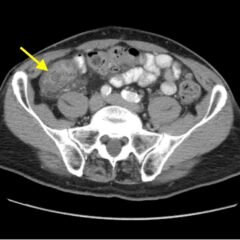

Although uncommon, acute aortic dissections are a life-threatening, cannot miss diagnosis for the emergency medicine clinician. Point of care ultrasound can play an integral role in the initial work up of the undifferentiated patient. While not initially utilized to make the diagnosis of aortic dissection, the ultrasound images obtained in this case describe key findings on ultrasound vital for an emergency clinician to recognize. It is essential for emergency medicine clinicians to differentiate an aortic dissection from other causes of chest pain and abdominal pain because the quick mobilization of resources plays a key role in the management and outcome of such patients.

Aortic dissection, vascular, dissection flap, back pain, point of care ultrasound, POCUS.